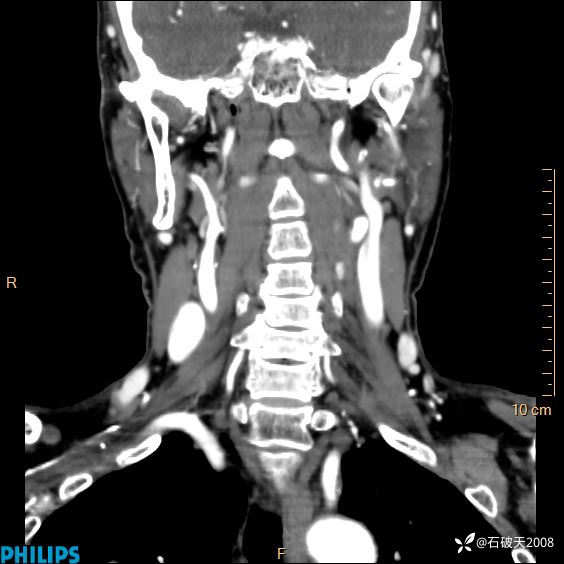

动脉期